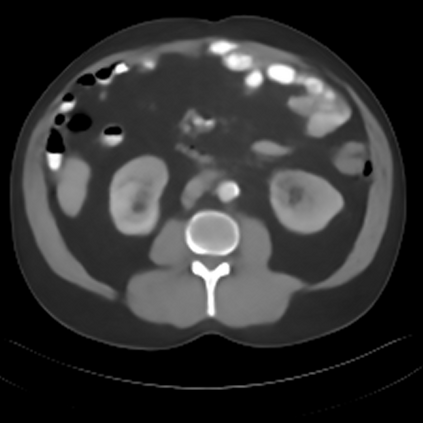

Sparse-view computed tomography (CT) -- using a small number of projections for tomographic reconstruction -- enables much lower radiation dose to patients and accelerated data acquisition. The reconstructed images, however, suffer from strong artifacts, greatly limiting their diagnostic value. Current trends for sparse-view CT turn to the raw data for better information recovery. The resultant dual-domain methods, nonetheless, suffer from secondary artifacts, especially in ultra-sparse view scenarios, and their generalization to other scanners/protocols is greatly limited. A crucial question arises: have the image post-processing methods reached the limit? Our answer is not yet. In this paper, we stick to image post-processing methods due to great flexibility and propose global representation (GloRe) distillation framework for sparse-view CT, termed GloReDi. First, we propose to learn GloRe with Fourier convolution, so each element in GloRe has an image-wide receptive field. Second, unlike methods that only use the full-view images for supervision, we propose to distill GloRe from intermediate-view reconstructed images that are readily available but not explored in previous literature. The success of GloRe distillation is attributed to two key components: representation directional distillation to align the GloRe directions, and band-pass-specific contrastive distillation to gain clinically important details. Extensive experiments demonstrate the superiority of the proposed GloReDi over the state-of-the-art methods, including dual-domain ones. The source code is available at https://github.com/longzilicart/GloReDi.